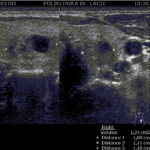

Ultrazvuk je morfološka pretraga koja koristi ultrazvučne valove za prikaz štitnjače. Ovom pretragom analiziramo građu i veličinu štitnjače, te otkrivamo eventualno prisutne morfološke promjene u štitnjači, kao što su čvorovi (kvržice), ciste, upalne promjene, te mjerimo veličine istih. Pomoću ultrazvuka uvijek je potrebno pregledati vrat i pripadajuće limfne čvorove čije povećanje može biti vezano za bolesti štitnjače.

U sklopu Centra za štitnjaču Poliklinike Lacić nabavljen je najnoviji američki ultrazvučni aparat sa color Dopplerom Philips Affiniti 70, koji je opremljen jedinstvenim „PureWave“ ultrazvučnim sondama. Tehnologija izrade tzv. „single crystal“ ili „PureWave“ ultrazvučnih sondi omogućuje duboku penetraciju što omogućuje bolju vizualizaciju štitnjače i svih struktura vrata. Philips Affiniti 70 ultrazvučni sustav je jedini sustav u klasi koji može koristiti „single crystal“ ili „PureWave“ tehnologiju. Čisti, uniformni „PureWave“ kristali imaju 85% bolju učinkovitost prilikom emitiranja i primanja ultrazvučnih zraka nego klasični piezoelektrični materijali. Ova izuzetna tehnologija omogućuje naprednu penetraciju uz izvrsnu rezoluciju u dubljim dijelovima slike, čime se postiže vrhunski prikaz štitnjače i svih struktura vrata. Time se omogućuje još točnije mjerenje svih morfoloških kao i hemodinamskih parametara. Na taj način smo u mogućnosti još ranije otkrivati bolesti štitnjače a samim time ih onda i bolje liječiti.